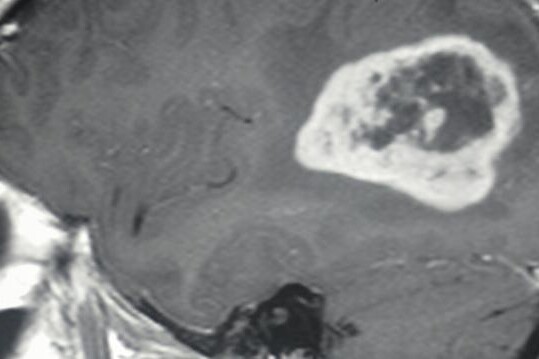

Základní diagnostickou metodou u glioblastomu je magnetická rezonance, která je schopna zobrazit expanzivně se chovající útvar. Další diagnostickou metodou je CT, tedy počítačová tomografie, která není tak přesná jako předchozí metoda, avšak je schopna lokalizovat nádor a určit jeho velikost,strukturu a vztah k okolním tkáním, nebo orgánům. Aby však bylo možné s jistotou určit diagnózu glioblastomu, je nutná histologická verifikace. To znamená, že je nutné získat vzorek tkáně z podezřelého útvaru punkcí.